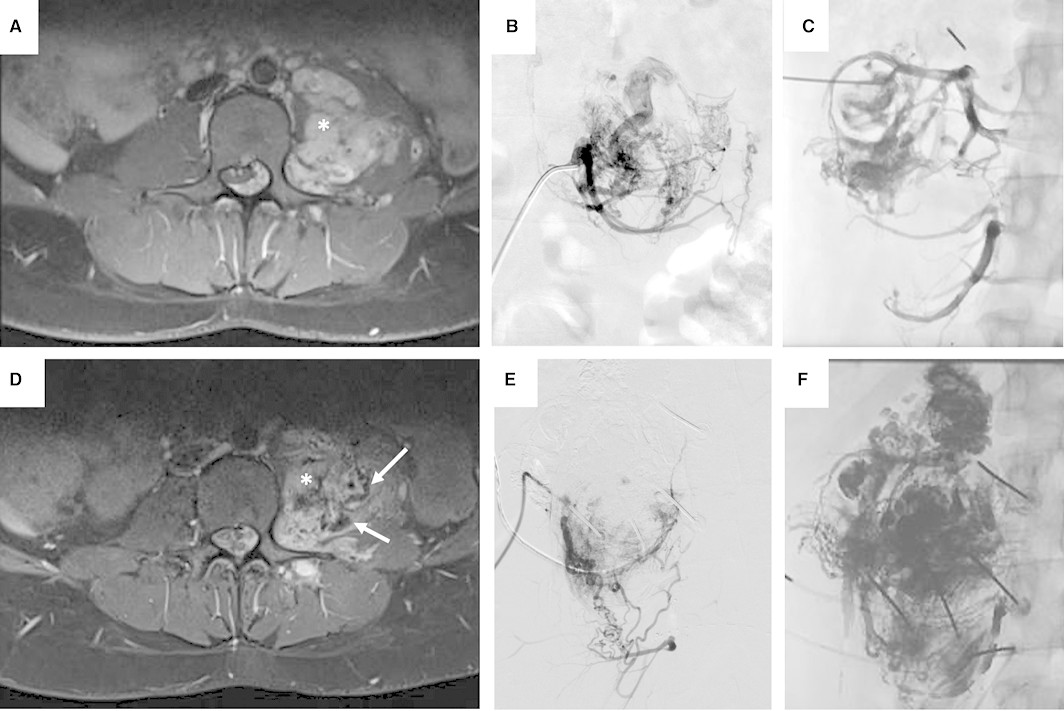

Schmidt et al. on extracranial #VascularAnomalies driven by #RAS/#MAPK variants: Spectrum and genotype-phenotype correlations. Vanessa F. Schmidt, MD, MHBA, EDiR #LMUradiology #APOLLON doi.org/10.1161/JAHA.1…

Schmidt et al. on extracranial #VascularAnomalies driven by #RAS/#MAPK variants: Spectrum and genotype-phenotype correlations. <a href="/VanessaFSchmidt/">Vanessa F. Schmidt, MD, MHBA, EDiR</a> #LMUradiology #APOLLON

doi.org/10.1161/JAHA.1…

Comparison of patients with various PVs in genes of the RAS/MAPK pathway reveals potential associations with certain morphological and clinical phenotypes. #AHAJournals Vanessa F. Schmidt, MD, MHBA, EDiR ahajournals.org/doi/10.1161/JA…

Comparison of patients with various PVs in genes of the RAS/MAPK pathway reveals potential associations with certain morphological and clinical phenotypes. #AHAJournals <a href="/VanessaFSchmidt/">Vanessa F. Schmidt, MD, MHBA, EDiR</a> ahajournals.org/doi/10.1161/JA…